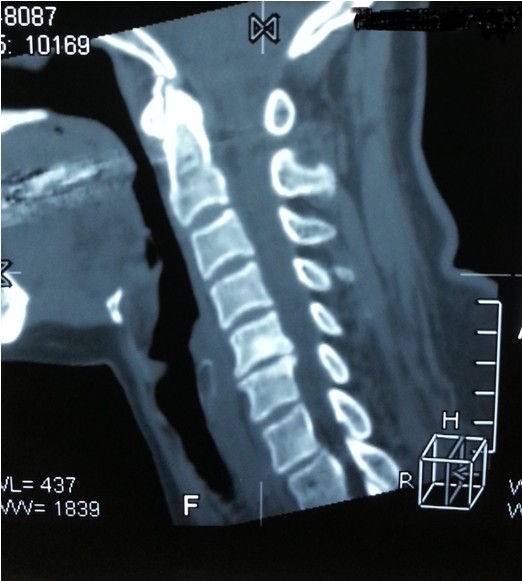

我院副院長兼脊柱科主任劉志安詢問病史后,詳細(xì)查體并攝片,發(fā)現(xiàn)患者是頸椎間盤突出,骨質(zhì)增生,壓迫頸椎神經(jīng),引起頸肩部酸脹難忍,雙手麻木乏力,若不盡快處理,癥狀將進(jìn)一步加重,建議患者盡早手術(shù)治療,否則將喪失最后的手術(shù)時(shí)機(jī),有致癱瘓的可能。

一開始,處于對手術(shù)以及住院費(fèi)用的恐懼,患者要求保守治療,可是如此嚴(yán)重的椎間盤突出,保守治療根本無法解除對頸椎的神經(jīng)的壓迫。劉副院長詳細(xì)向患者講述其病情起因,發(fā)展,變化,轉(zhuǎn)歸,并表示,患者頸椎手術(shù)總費(fèi)用預(yù)計(jì)在5萬以內(nèi),報(bào)銷后自費(fèi)約4萬左右,考慮患者家庭困難,可聯(lián)系紅十字基金會(huì)予以適當(dāng)?shù)难a(bǔ)貼,考慮再三,最終患者選擇到我院手術(shù)治療。手術(shù)結(jié)束后,患者慢慢開始恢復(fù),頸肩部酸脹不適癥狀消失,雙手麻木乏力癥狀較術(shù)前大為緩解,兩周后出院,患者及家屬對手術(shù)治療效果,醫(yī)生護(hù)士服務(wù)態(tài)度,以及花了3萬元就解決困擾多年的疾病均表示非常滿意。